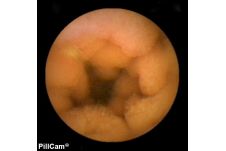

Der Dünndarm galt bis zur Einführung der sogenannten "Pillenkamera" als weitgehend uneinsehbarer Bereich. Dank einer innovativen Schluck-Kapsel mit Kamera und eigener Lichtquelle, die ohne eigenen Antrieb durch den Körper reist und währenddessen Bilder liefert, hat sich dies grundlegend geändert. Auch in der Klinik Mallersdorf wird diese Untersuchung durchgeführt, besonders zur Dünndarmdiagnostik.

Mit der Kapselendoskopie ist eine bildgebende Untersuchung des Dünndarms in einer für den Patienten schonender Weise möglich. Dabei wird eine Kapsel in Größe einer Penicillin-Kapsel geschluckt. Die integrierte Kamera nimmt während ihrer Reise durch den Magen-Darm-Trakt über einen Zeitraum von 8 Stunden Bilder auf und sendet sie an einen Rekorder. Die Kapsel wird dann auf natürlichem Wege ausgeschieden, die aufgezeichneten Bilder können mit einem speziellen Computerprogramm ausgewertet und befundet werden.

Die Kapselendoskopie wird besonders im Bereich des im Rahmen der Magen- und Darmspiegelung nicht einsehbaren Dünndarmbereichs verwendet. Sie hilft bei der Suche nach Blutungsquellen, chronisch entzündlichen Darmerkrankungen oder Tumoren.

Voraussetzung für eine Kapselendoskopie ist stets eine vorausgehende Magen- und Darmspiegelung. Sie ist also kein Ersatz, sondern eine Ergänzung für letztere.